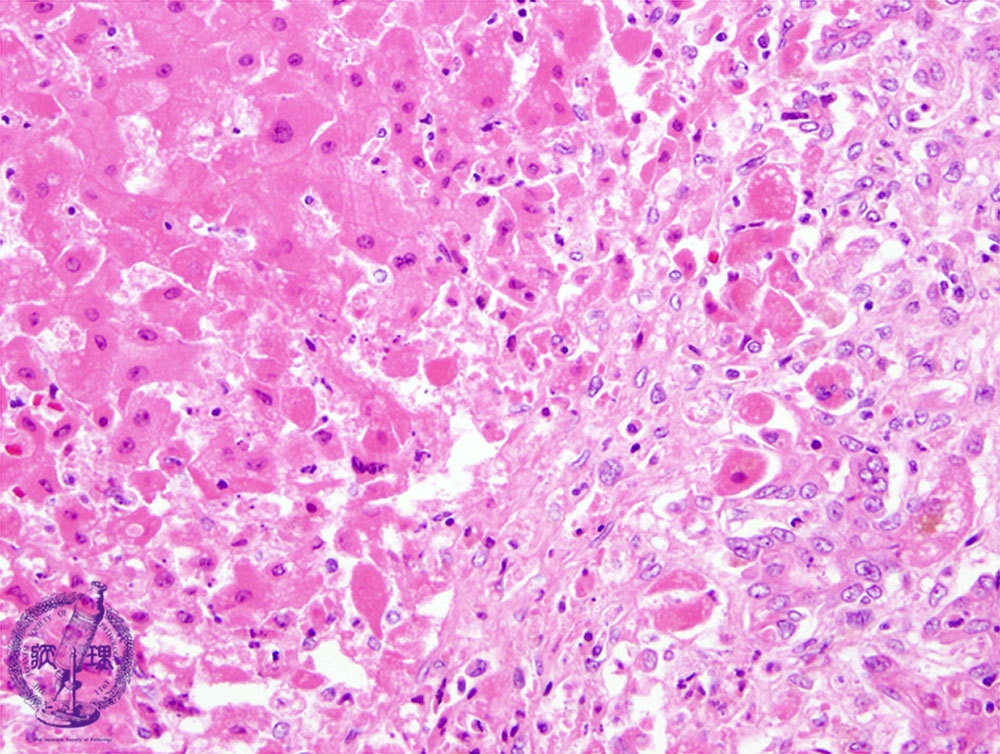

- ★(3)Fulminant hepatitis

Microscopic image (HE stain, high power): There is an interface between necrotic (left of the dotted line) and non-necrotic areas; the necrotic hepatocytes are swollen and more eosinophilic.